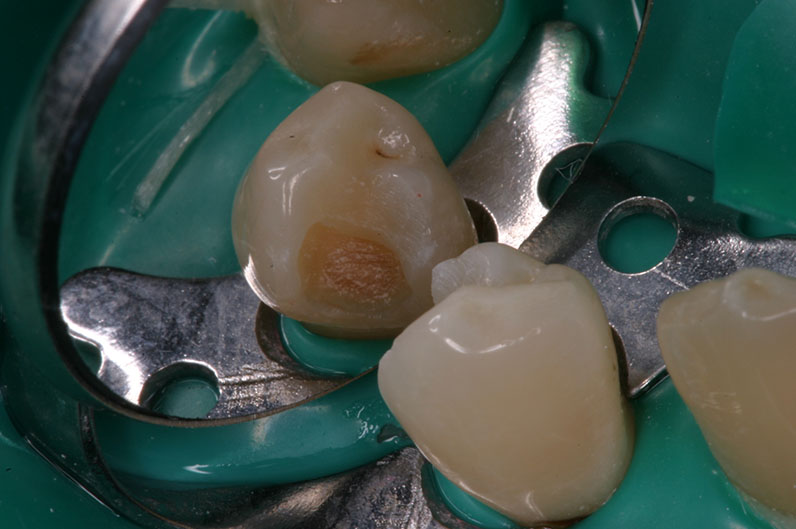

после экскавации кариеса